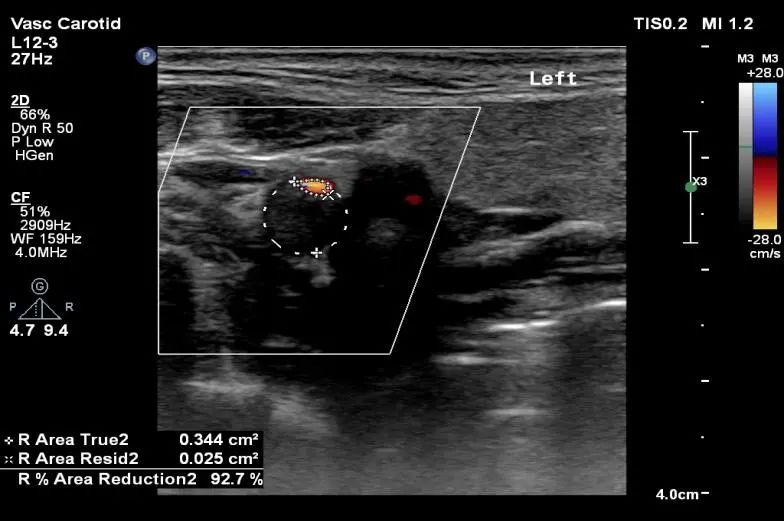

“健康”体检者。颈动脉超声提示颈动脉重度狭窄。TCD提示颅内侧支循环代偿充分。无创的头颈血管超声的一体化评估是筛查脑血管病高危人群的首选,是“前哨兵”。